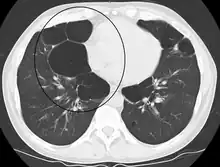

A chest X-ray is not useful to establish a diagnosis of COPD but it is of use in either excluding other conditions or including comorbidities such as pulmonary fibrosis and bronchiectasis. Characteristic signs of COPD on X-ray include hyperinflation (shown by a flattened diaphragm and an increased retrosternal air space) and lung hyperlucency.[5] A saber-sheath trachea may also be shown that is indicative of COPD.[110]

A CT scan is not routinely used except for the exclusion of bronchiectasis.[5] An analysis of arterial blood is used to determine the need for oxygen supplementation and assess for high levels of carbon dioxide in the blood; this is recommended in those with an FEV1 less than 35% predicted, those with a peripheral oxygen saturation less than 92% and those with symptoms of congestive heart failure.[111] WHO recommends that all those diagnosed with COPD be screened for alpha-1 antitrypsin deficiency.[42]

Other surgeries